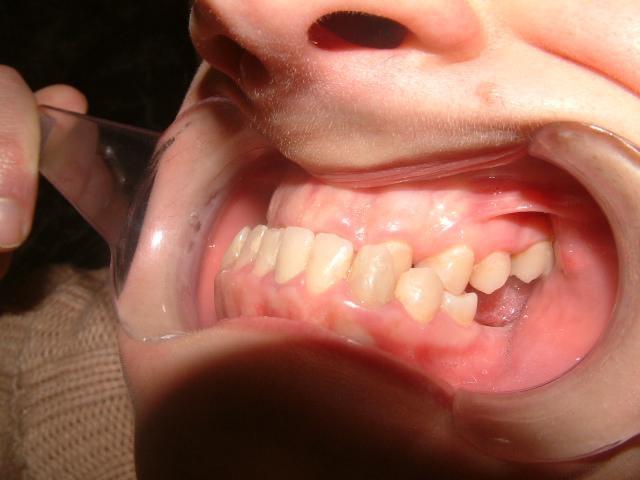

1η περίπτωση

Αρχική οδοντοσκελετική κατάσταση παιδιού με προγναθισμό άνω γνάθου και έντονη οριζόντια πρόταξη άνω τομέων Η σημασία της στοματικής υγιεινής και ορθοδοντικής

026

πρόληψης

027 Αμέσως μετά το τέλος της ορθοδοντικής θεραπείας. Οι αλλαγές στην οδοντική του σύγκλειση αλλά και στο πρόσωπο είναι εμφανείς 15 χρόνια μετά την αρχική περάτωση της θεραπείας, το αποτέλεσμα παραμένει σταθερό και ο ασθενής απέκτησε ένα υγιές και αρμονικό χαμόγελο και πρόσωπο. Η σημασία της στοματικής υγιεινής και ορθοδοντικής πρόληψης